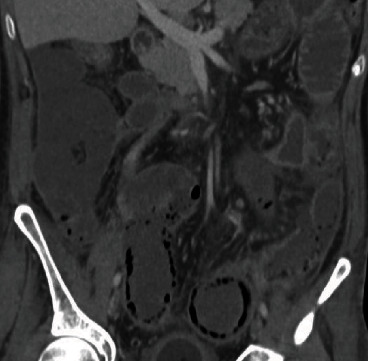

Imaging findings of pneumatosis intestinalis posttransplant are unique as compared to PI seen in other scenarios such as bowel ischemia. PI in posttransplant patients has a bubble-like/expansile appearance with a significant amount of air within the bowel wall (Figures 1 and 2). In these patients, it is helpful to view the pneumatosis on lung windows in order to properly assess its extent (Figure 3). In contrast, for PI in a patient with intestinal ischemia (Figure 4), imaging findings show more of a thin rim of gas bubbles within the submucosa without the expansile appearance. Although posttransplant PI can appear as a thin layer of gas, it would be unusual for intestinal ischemia to appear as bubble-like/expansile. Thus, if the bubble-like/expansive appearance of PI is seen, it may support a benign etiology and clinical course.

(a) Abdominal radiograph, (b) coronal CT, and (c) axial CT. PI of the ascending and transverse colon with “bubbly/expansile” wall appearance with extensive air cysts in the subserosal and submucosal layers.

(a) Abdominal radiograph, (b) coronal CT, and (c) axial CT. Pneumatosis intestinalis of the ascending and proximal transverse colon displaying circumferential bubbly/expansile appearance of the colon wall. Notice also the presence of subcutaneous emphysema.